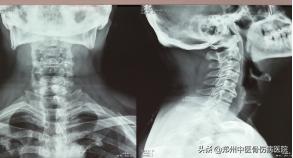

颈部生理曲度变直,活动稍受限,颈、肩部肌肉稍紧张,其中双侧颈肩部至三角肌处痛点明显。左侧椎间孔挤压试验(+)

辅助检查:颈椎MRI:C3/4--C5/6椎间盘退行性病变